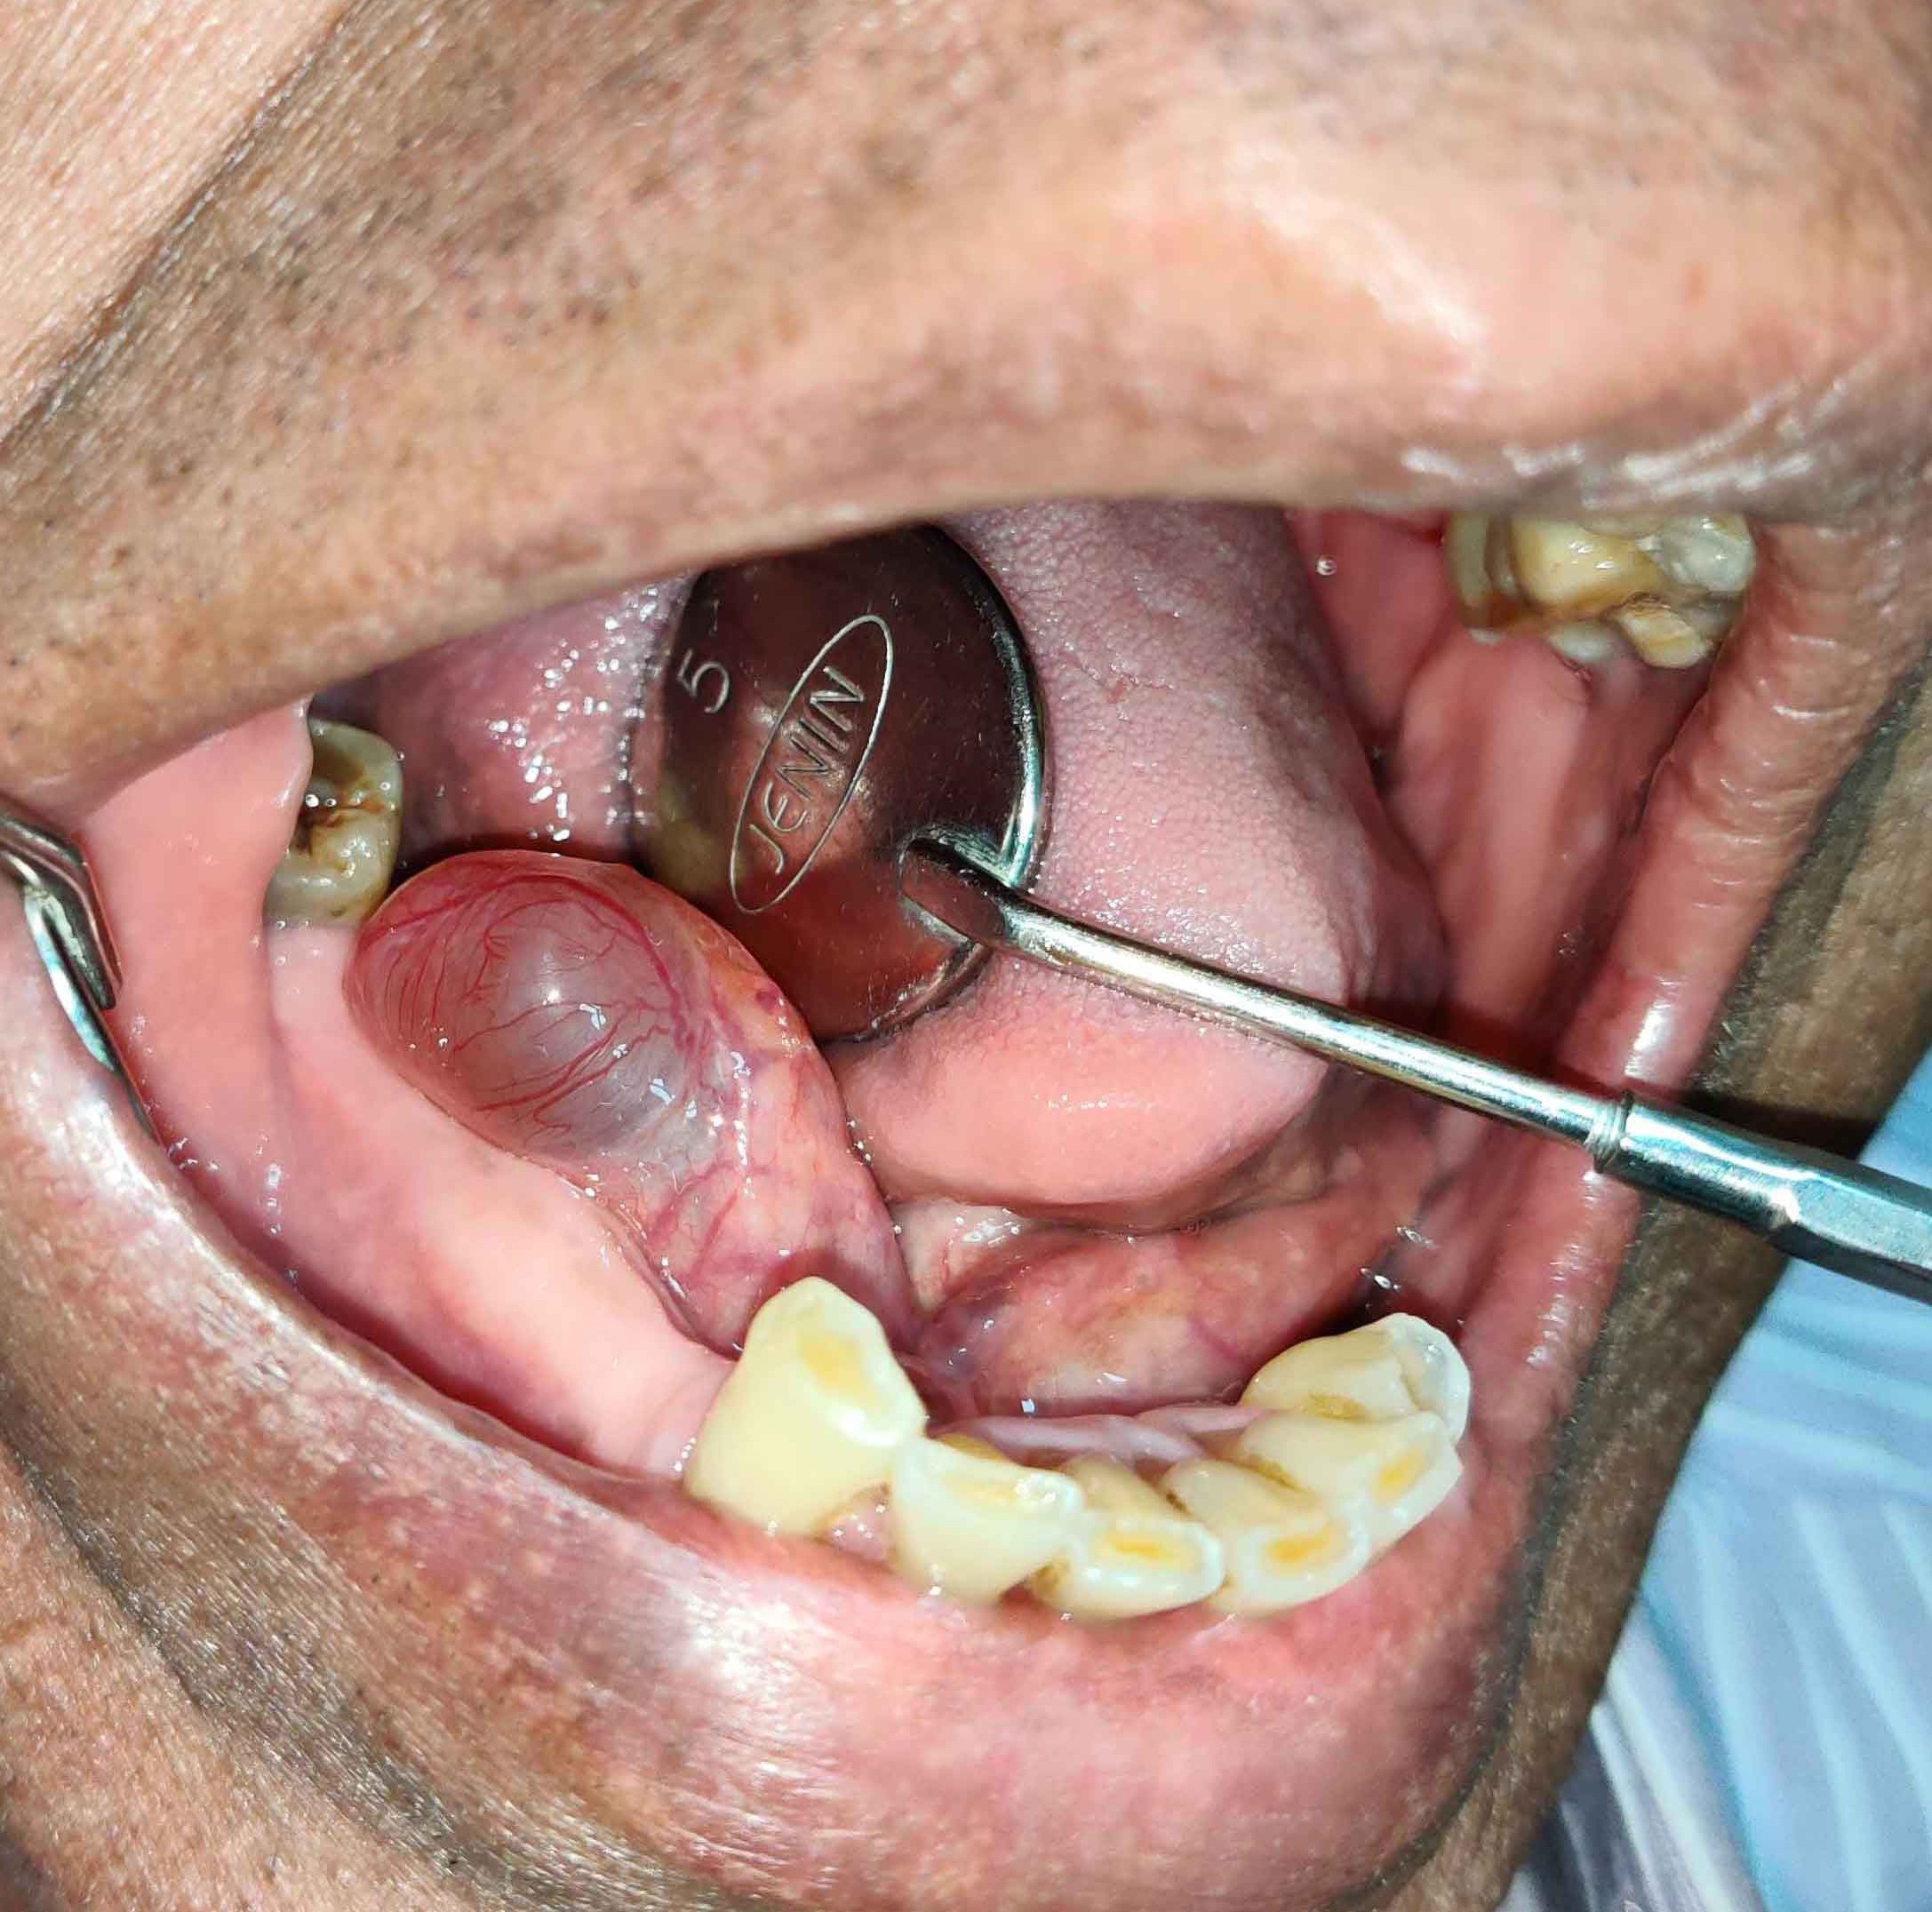

There are numerous pathologies that can develop in the jaws ranging from small cysts which are incidentally found on routine radiographic examination to large cysts which can cause facial swellings or asymmetry. To understand the type of pathology we usually do a biopsy. The biopsy may be an Incisional biopsy or an excisional biopsy. This is based on the surgeon’s opinion and the nature and the size of the lesion or growth in the jaws.

Using laser we can do the biopsy as a bloodless procedure. The vast array of pathologies, and the wide range of treatment they require ranging from simple laser excision to jaw resection is why you have to consult an oral and maxillofacial surgeon as early as you see something abnormal in your face or inside your mouth. The abnormality can even be as simple as a non healing ulcer or a small tissue tag inside the mouth.